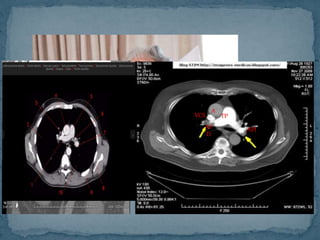

ANGIOTOMOGRAFIA

COMPUTARIZADA

Actualmente la angio-TC puede sustituir a la gammagrafía pulmonar

(grado de recomendación B)